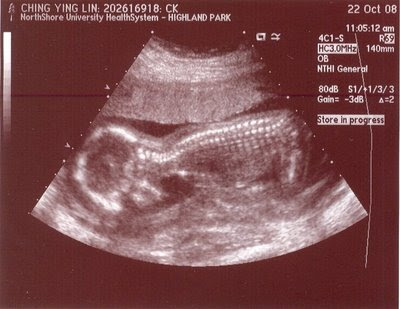

早上去照超音波,終於看到小寶的樣子了,雖然跟想像中的不太一樣,也跟國家地理頻道或 Discovery Channel 那種漂亮的電腦繪圖不同,但~終於看到了。小寶似乎在睡覺,沒有辦法看到完整的心室發育,所以還要去照一次。但醫生很有技巧地往雙腿中間探索,根據專業的判斷,那細小多出來的一根棒棒,應該就代表是男孩了。如果下次照,性別改了的話,我可能會昏倒。

當你看不見時,你的擔心是很多的:會不會照出來有三條腿?會不會沒有心跳?發育得好不好?不過這些疑惑都在電腦螢幕被解除了。接下來,要繼續想名字了...